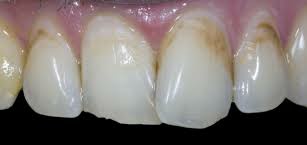

5 класс - это полости, расположенные в пришеечной области всех зубов.

1. Кариес в стадии пятна - потеря естественного блеска, появление белых, светло-коричневых и темно-коричневых. Здесь есть два пути развития:

1)пятна вообще никак не изменяются долгие годы, обычно при должной гигиене и наблюдении.

2) на месте коричневого пятна образуется полость. Все происходит на этом этапе в поверхностных и подповерхностных слоях эмали практически бессимптомно.

2. Поверхностный кариес: на месте пятна образуется полость с нарушением целостности тканей. Возможны кратковременные реакции на сладкое, кислое, холодное. Кариес приближается к эмалево-дентинной границе.